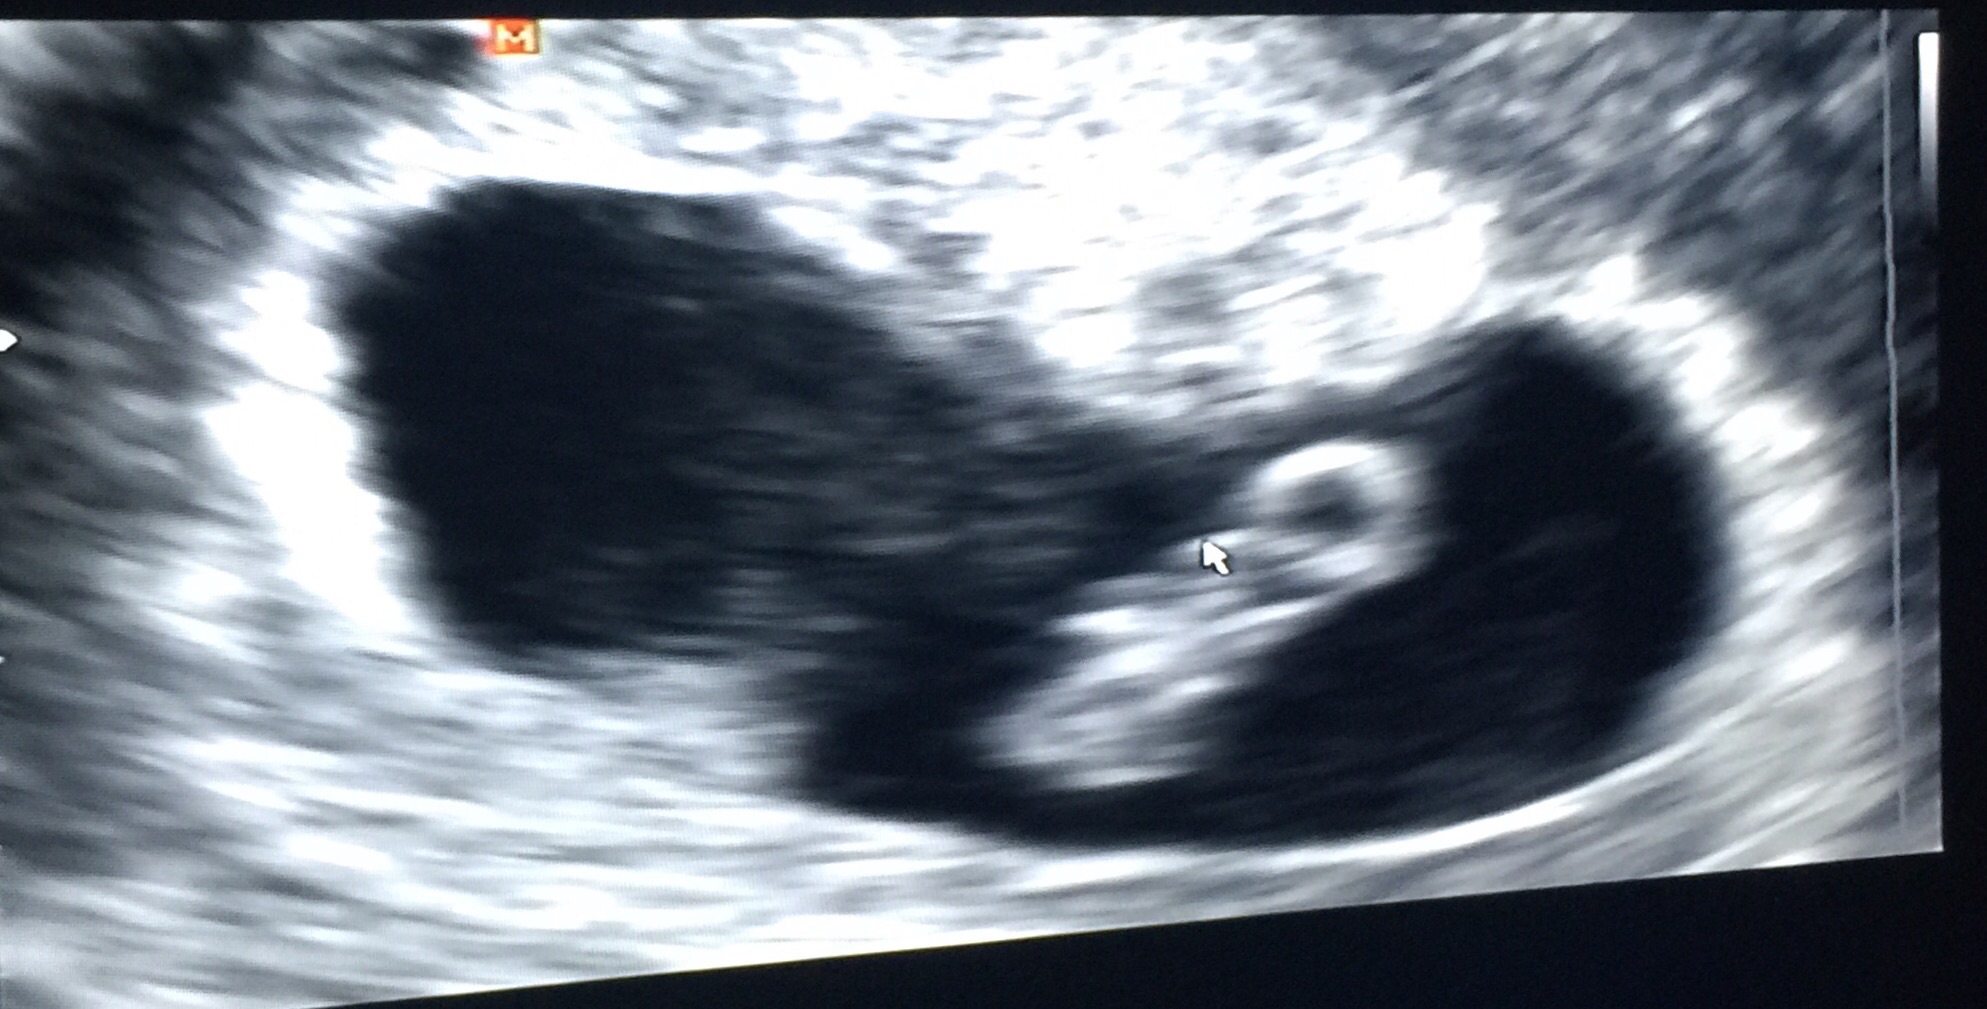

• I'm 10 weeks today. My due date is April 7th. This picture is actually from my second ultrasound that I got yesterday. I got my first one done at 7 weeks and 5 days due to some minor bleeding which they determined was from a small blood blister in my uterus. As of yesterday we got the good news that the blood blister has shrunk dramatically! So now my appointments will continue on as normal. The baby's heartbeat was 156 at my first appointment and yesterday it was 175. I'm not sure I can accurately describe how happy I was to see my little baby moving around on the screen yesterday! It's truly something magical.